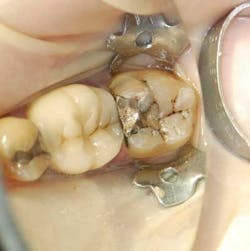

A 55-year-old male patient presented with a chief complaint of occasional hot and cold sensitivity involving his lower molar. Upon clinical examination, it was determined he had a failing amalgam and undermined mesial buccal cusp involving his second molar (Fig. 1). As per the Morgan and Presley’s prewedge protocol, a medium wedge was placed between the molars to initiate separation and protect the papilla. Upon removal of the old restoration and decay, it was decided to restore this tooth with a posterior composite material using the ABC Wedge. With a little imagination, this wedge looks like an elephant’s head and its parts will be described as such. The ears were designed to support the sectional band in three dimensions (3-D) and prevent the sectional rings from crushing in the matrix band (Fig. 2). The elephant’s trunk is analogous to the anatomic wedge. Two wedges were used from the buccal and lingual surfaces, and the curved trunks slide past each other to seal off the gingival floor (Fig. 3). A central groove is located on the back between the ears to line up the sectional separating ring and directs the pressure interproximally for maximum separation. The tooth was then easily restored in incremental layers, trimmed back, and the bite was adjusted (Fig. 4).

Fig. 1 — Failing amalgam and undermined cusp.